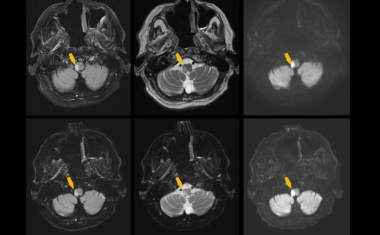

Eine neue MRT-Technik in der Universitätsmedizin Mainz erkennt Schlaganfälle in kürzester Zeit.